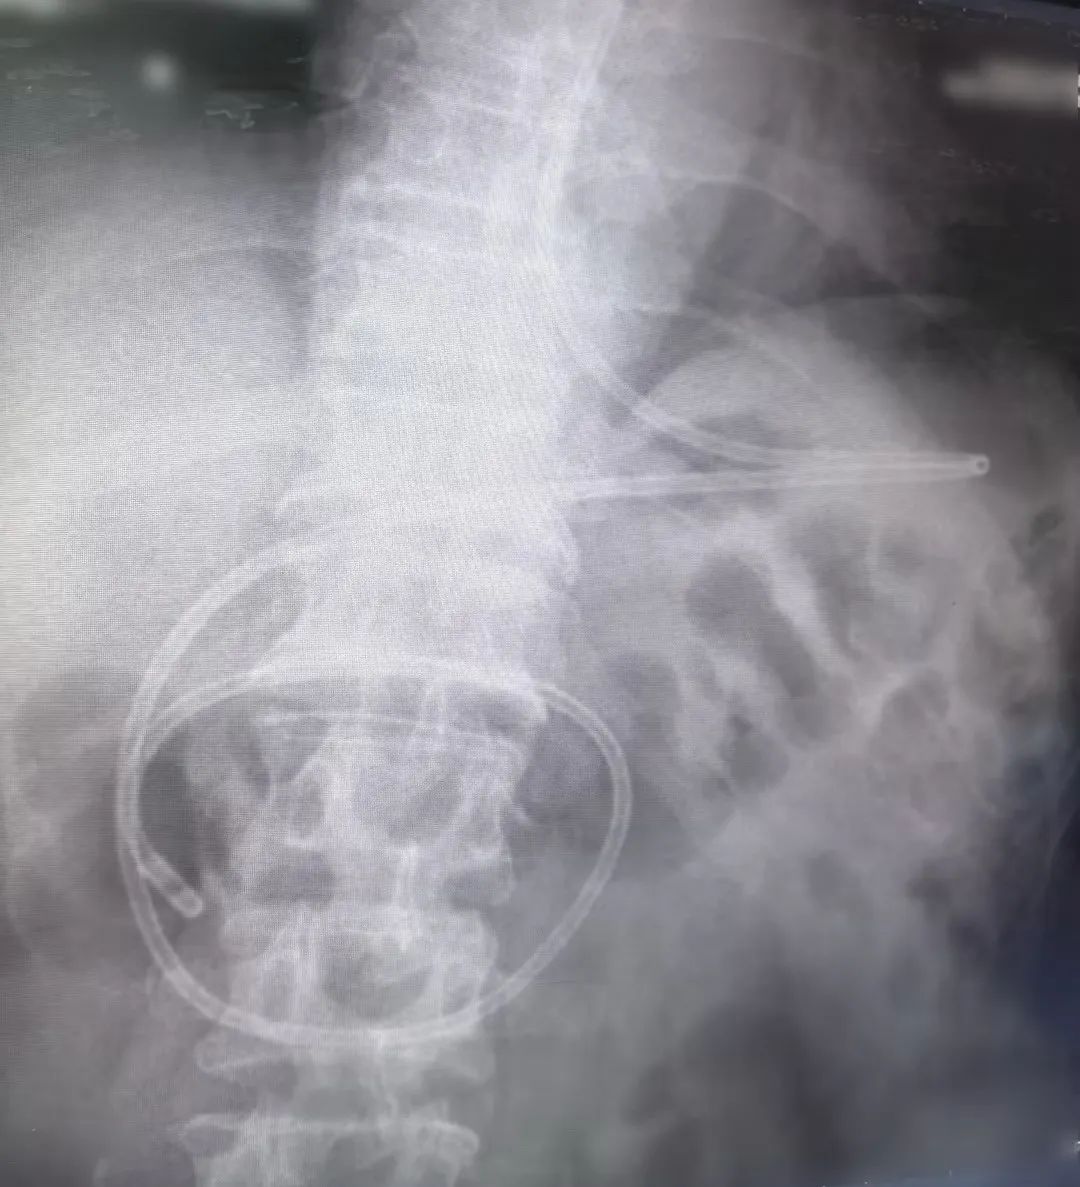

近日,我院重症医学科(ICU)护理团队在主管护师马瑛的带领下,成功为一名重型颅脑损伤患者实施了“床旁徒手盲插鼻空肠管”技术,标志着我院在危重症患者肠内营养支持领域取得突破性进展,护理技术水平再上新台阶。

传统的鼻空肠管置入方法需要在X线或胃镜引导下进行,存在操作复杂、耗时长、患者痛苦大等缺点。而徒手盲插鼻肠管技术无需借助任何辅助设备,仅凭护士的手感和经验即可将鼻肠管准确置入患者空肠内,具有操作简便、成功率高、患者舒适度高等优点。

此项技术的成功开展,是我院护理团队不断探索、勇于创新的成果,也体现了我院在危重症患者护理方面的综合实力。该技术的推广应用,为危重症患者快速得到营养治疗打开了一条便捷通道,解决了患者长期需要肠内营养支持的“棘手问题”,也给更多患者提供了更安全、便捷、有效、经济的医疗服务。